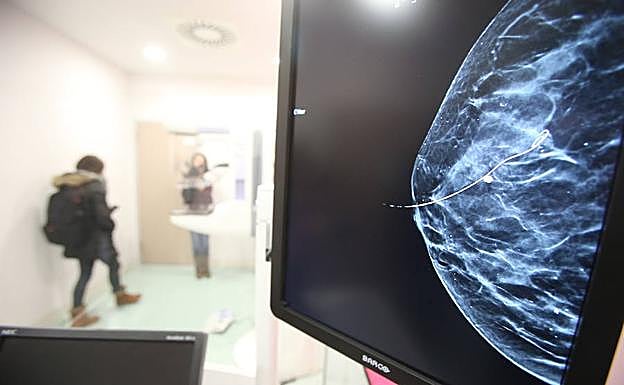

Imagen de una mMamografía.

Un alto porcenteje de pacientes con cáncer de mama y pulmón podrían evitar la quimioterapia

Un alto porcentaje de pacientes de cáncer de mama y pulmón podrían evitar la quimioterapia e incluso tener una mayor esperanza de vida, según dos estudios difundidos este domingo en la reunión anual de la Sociedad Estadounidense de Oncología Clínica, en Chicago, EE UU.